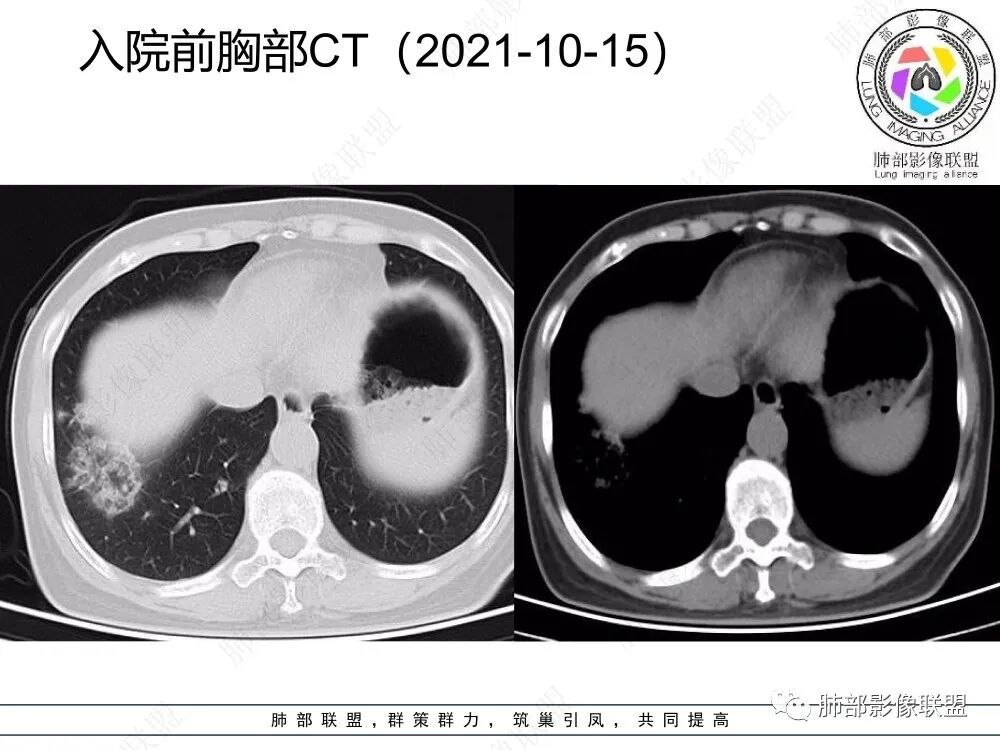

2、CT表现为两肺下叶结节影、斑片影、磨玻璃影,沿支气管血管束分布,部分支气管壁显示增厚。粗略一看部分病灶内似可见“细网格影”,但是仔细观察,可发现此“细网格影”不同于我们常见的“细网格影”,尤其是右肺下叶病灶,可以观察到病灶内部的网格上有高密度结节感或颗粒感,部分层面见“反晕征”,且反晕的边缘亦可观察到结节感。未见胸腔积液。

2、但影像学具有一定的特征性,病变一般沿支气管树分布或小叶分布,一般上肺多于下肺。部分病例呈双肺“雪花样”分布,较有特点。部分病例可表现为“反晕征”。除以上表现外,间质性肺结核还可以表现为:1 肺小叶间质内异常,表现为小叶间质内网状影,呈网结节样改变,与正常肺分界较清晰是其特点。2 支气管血管束增粗和小叶间隔增厚。3 磨玻璃影。

2、好发部位与其它结核类似,上叶及下叶背段为主。 3、烟花征,反晕征,环呈结节状,可以伴随空洞,树芽征,结节灶,胸水。(反晕征:一般周围实性环形高密度影,中央呈低密度;一般环超过圆的3/4,结核的环主要是小叶核心结节组成,类似于多发树芽征聚集,边缘结节感。中央的晕:可以是腺泡结节,树芽征,细网状,磨玻璃影,很少正常,主要成分是小叶内间质增厚、小叶核心结节、肺泡内病变。)其实也体现了结核的多灶性、多态性特点。